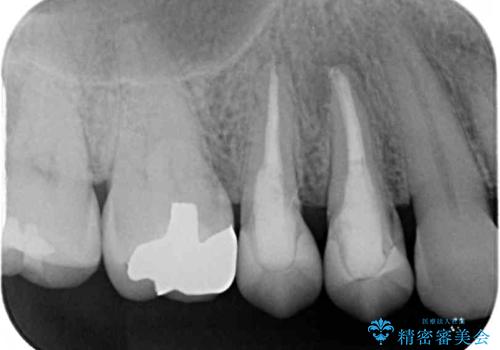

- クラウンが割れて治療を行っていたものの、途中で放置してしまったとのことで来院された患者様です。

根管治療を行った後に、ガラス系セラミッククラウンにて補綴することとしました。

透明感のある自然な仕上がりとなり、患者様には大変満足していただきました。